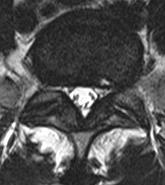

Discopathie MODIC 1: Notez le respect des corticales, la masse des parties molle antérieure en hyposignal T2 (disque extériorisé) et la prise de contraste linéaire du disque